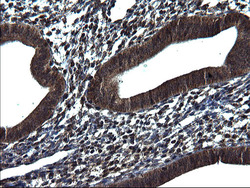

Immunohistochemistry

TA590417 IHC

Full details

Method: